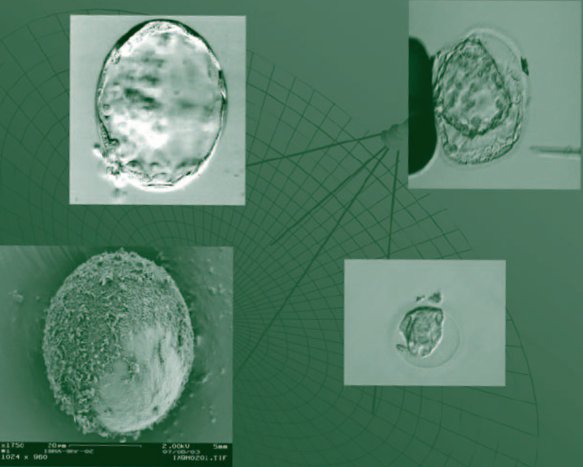

Préservation de la Fertilité

avant traitement anti-cancéreux.21 juin 2012Amphitéatre Pasquier - Faculté de Médecine - Université Pierre et Marie Curie. Site Les Cordeliers, 15 rue de l'Ecole de Médecine 75006 PARIS Présidée par Mickael Grynberg. Comité d'organisation : R Frydman, M Grynberg, J.F. Velez de la Calle. |